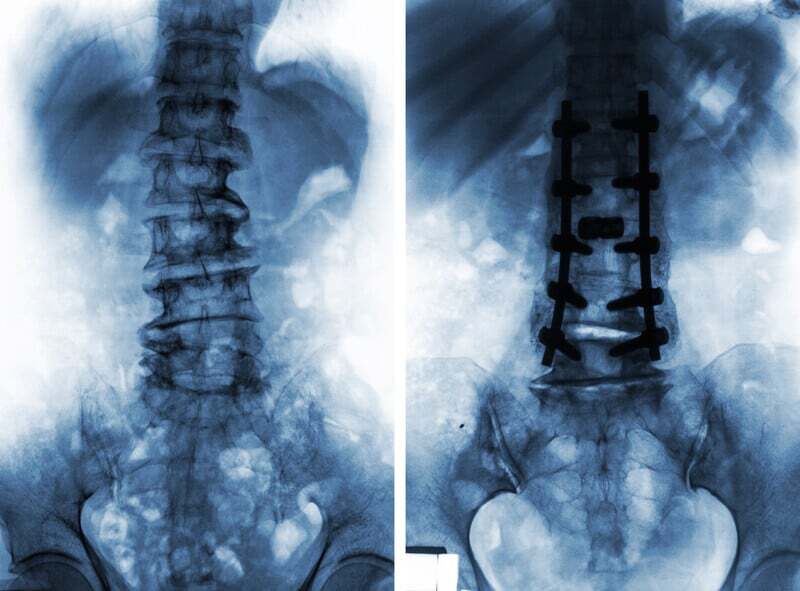

A July 2021 editorial (2) repeats the confusing problem of true pain diagnosis and which surgery should go first. “Several studies have reported that patients with a previous lumbar arthrodesis (fusion) undergoing hip replacement have lower patient-reported outcomes and greater revision rates compared with patients without previous lumbar surgery, and similar to its effect on outcomes after hip replacement, lumbar spine disease can compromise outcomes after hip arthroscopy. On the other side of the coin, replacement has been shown to improve low back pain in patients with concomitant hip osteoarthritis.”

The option to have lumbar spinal surgery and hip replacement at the same time is clearly one that is not recommended for obvious reasons. So a decision has to be made. Spinal surgery or hip replacement surgery? One has to come first and one has to wait.

A March 2024 study (15) sought to add input into the “increasing debate among orthopaedic surgeons over the temporal relationship between lumbar spinal fusion and total hip replacement for patients with hip-spine syndrome.” The researchers noted “few large studies have directly compared the results of patients who undergo lumbar spinal fusion prior to total hip replacement to those who undergo lumbar spinal fusion after total hip arthroplasty.” In a study of 716,000 patients. The researchers found lumbar spinal fusion first patients experienced significantly more postoperative dislocations at 90 days and 1 year compared to hip replacement patients. There were a similar number of revisions performed for spine first and hip first surgery patients at both 90 days and 1 year. At one year, lumbar spinal fusion first patients experienced more pneumonia and joint infection.